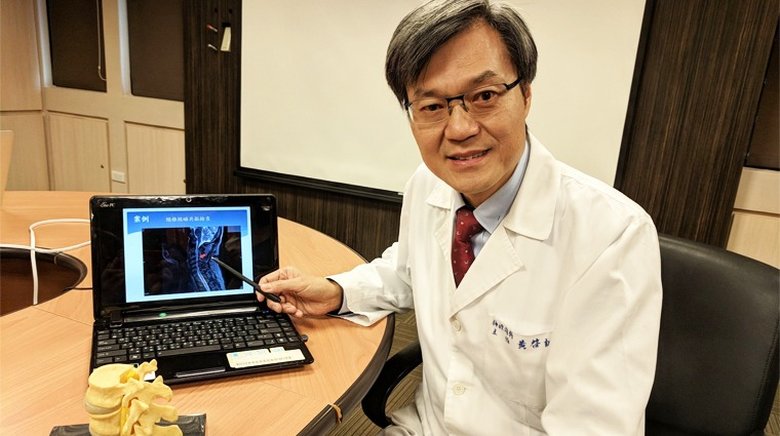

長安醫院骨科主任楊志鴻提醒民眾雅腰椎痠麻痛問題應盡速就醫、及早治療。(圖/長安醫院提供)

台中長安醫院骨科主任楊志鴻表示,患者的第2至第5節腰椎有很明顯的骨刺及椎間盤突出,也有勞動性側彎問題,這些都會造成神經受到壓迫,因此患者走路會有點一跛一跛的、下肢會痠麻痛。經評估後建議手術治療,術後王先生高興的說 : 「術後痠痛感減輕太多了,也大幅改善生活品質,非常滿意。」

楊志鴻說,傳統的椎體融合手術是靠X光機做判斷,因此神經損傷風險高,此次採用的微創脊椎減壓及椎體融合手術,在電腦斷層3D導航機器幫助下,能精準定位、提升手術的安全性,讓神經損傷機會趨近於零,也縮短癒合時間,因此病患在術後第2天就能下床走路。